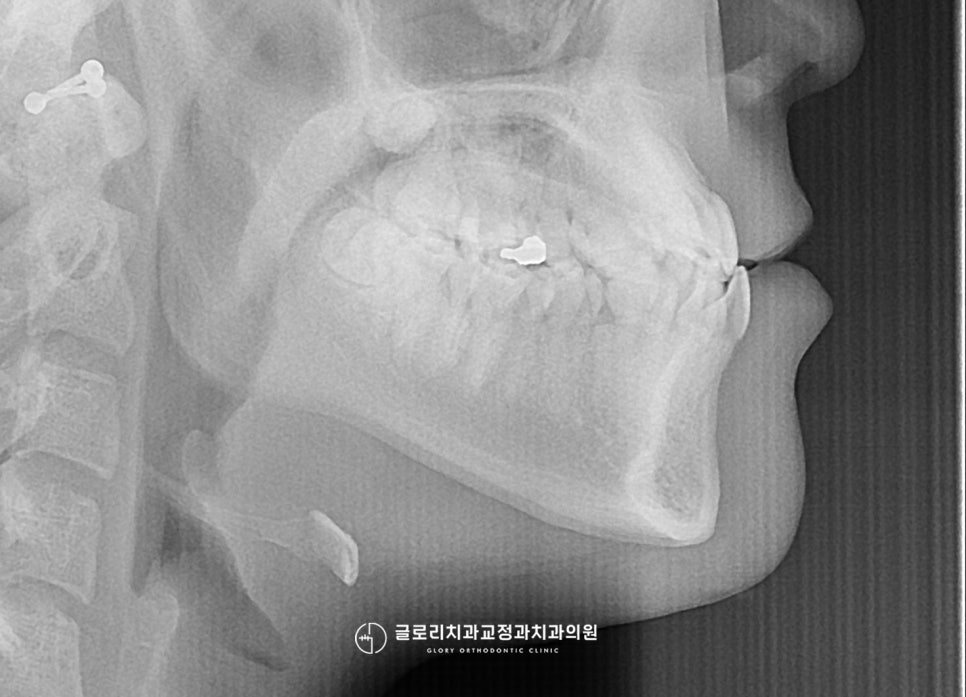

1. 초진: 20대 초반 여성

정확한 진단을 위해 구내를 먼저

환자께서 말씀하셨듯이 심한 덧니가

바로 눈에 띄는데요.

양쪽 위 송곳니가 위쪽으로 솟아

제 위치가 아닌 곳에서 자리 잡아

더욱더 도드라져 보입니다.

게다가 또 다른 문제점 또한

찾아볼 수 있었는데요.

앞니쪽을 보시면 어색한 듯 물려있는

형태를 관찰하실 수 있는데요.

보통 윗니가 아랫니를 덮는 자연스러운

피개 방식으로 되어있어야 되지만,

이 경우에는 거꾸로 물리는 반대교합을

나타내고 있었습니다.

이런 반대교합은 아랫니가 윗니를 덮어

아래턱이 전방으로 돌출되어 나올 가능성이 있는데요.

이렇게 아래턱이 전방으로 돌출되어 나온다면

주걱턱의 형태도 쉽게 볼 수 있습니다.

안모 사진에서도 역시나

아래턱이 돌출되어 나온 경향을

관찰할 수 있었습니다.